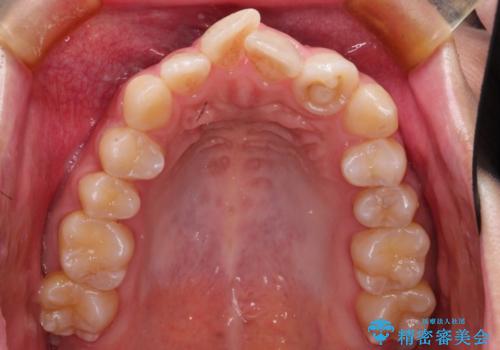

左上の前から2番目の歯が通常とは異なる形態をしており、左右対称にすることはできませんでしたが、インビザラインで周りに気づかれることなく矯正治療をおえることができ、満足していただけました。